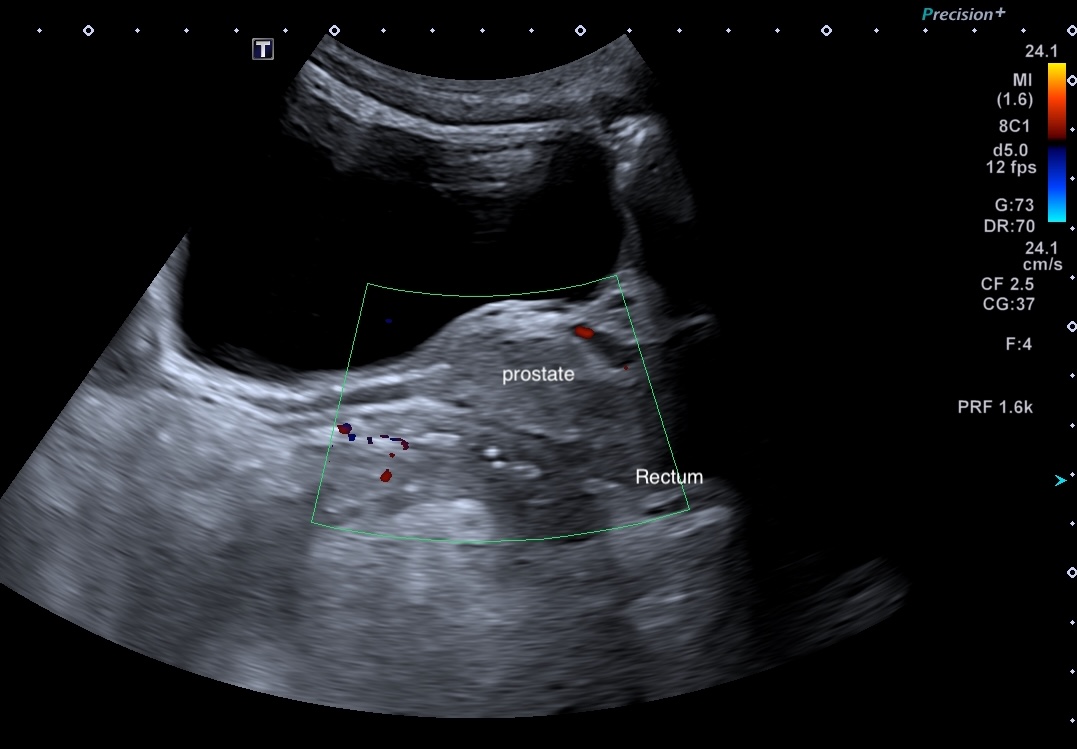

Maladie de Crohn, rectum (épaissisement asymétrique prédominant à la partie postérieure) coupe passant par la prostate

Même patient coupe longitudinale

Epaississement asymétrique prédominant partie postérieure (9 mm)

La voie transpérinéale permet d'observer le rectum dans 100 % des cas avec la sonde HF

Elle nécessite un appreentissage complet, car les images, les mouvements de la sonde différent totalement de la technique habituelle d'échographie intestinale

Le seuil d'épaississement du rectum est fixé à 4 mm